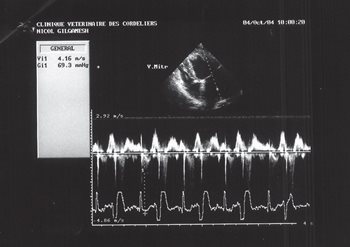

Figure 8: echocardiography (pulsed Doppler mode), left parasternal long axis image, four-chamber view: restrictive transmitral flow.

Echocardiography confirmed severe, mostly left-sided, chamber dilatation. The LA/Ao ratio was increased (figure 4) (LA/Ao = 2.7; normal < 1.6 [6]), as well as the LVEDD/Ao ratio (figure 5) (LVEDD/Ao = 3.1; normal < 1.8 [7]). Ventricular dilatation was also observed in M-mode during systole and diastole (figure 5) (LVEDD = 7.04 cm; normal < 4.4 cm [8]; LVESD = 4.04 cm;

normal < 2.9 cm [8]). The free side of the mitral valve leaflet was mildly thickened during diastole (figure 6) and systole (figure 7), and a small prolapse was seen (figure 7). Chordae tendinae were normal.

Transmitral flow was recorded in pulsed-wave Doppler echocardiography (figure 8) and showed a restrictive type (Appleton type 2, Em/Am= 2.04). A high velocity mitral regurgitation flow was recorded (Vmax=4.16m/s). All other flows (aortic, pulmonary and tricuspid) were within normal limits.

Figure 9: echocardiography (pulsed Doppler mode), left parasternal long axis image, four-chamber view: mitral regurgitation flow.